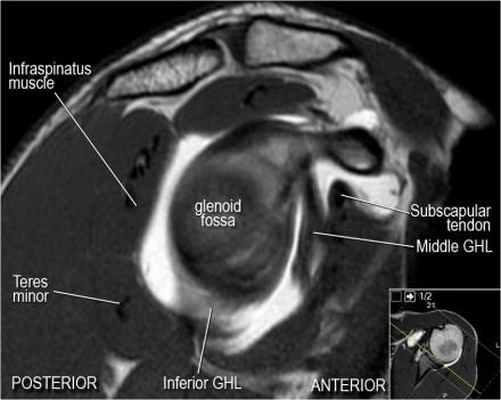

Изображение передних отделов плечевого сустава.

Сухожилие подлопаточной мышцы прикрепляется как к малому бугорку, так и к большому бугорку, давая поддержку длинной головке двуглавой мышцы в борозде двуглавой мышцы. Вывих длинной головки двуглавой мышцы плеча неизбежно приведет к разрыву части подлопаточной сухожилия. Манжета вращателей плеча состоит из сухожилий подлопаточной, надостной, подостная и малой круглой мышц.

Нормальная анатомия плечевого сустава в аксиальных изображениях и контрольный список.

- уровень средней плече-лопаточной связки и передних отделов суставной губы. Поищите комплекс Буффорда. Изучите хрящи.

- обратите внимание на волокна нижней плече-лопаточной связки. На данном уровне так же ищется повреждение Банкарта.